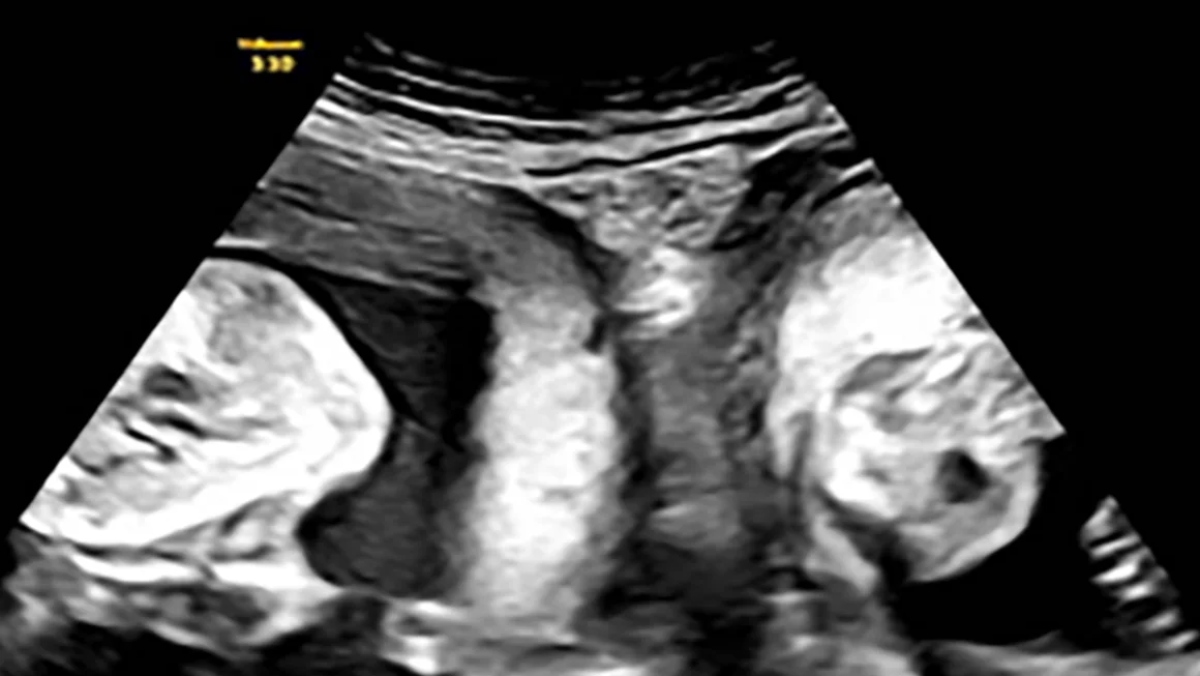

Η ιστορία της έγινε viral στα κινεζικά μέσα κοινωνικής δικτύωσης, με περισσότερες από 50 εκατομμύρια προβολές τις τελευταίες ημέρες. Το νοσοκομείο αποκάλυψε επίσης ότι η νεαρή μητέρα είχε μείνει έγκυος άλλη μια φορά αλλά είχε αποβάλλει. Τον Ιανουάριο, όμως, η Li έμεινε ξανά έγκυος και ανακάλυψε κατά τη διάρκεια ενός υπερηχογραφήματος ότι κυοφορούσε δίδυμα – ένα σε κάθε μήτρα.